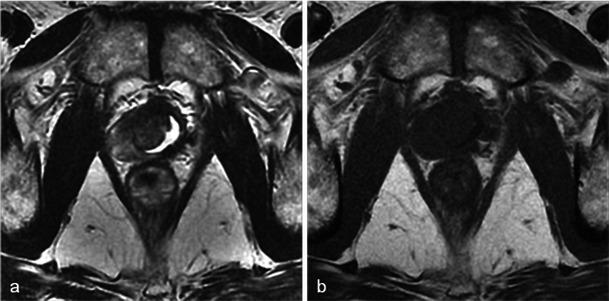

In this technique, a photosensitising agent is introduced intravenously, then activated by local laser illumination to induce tumour necrosis. Treatment efficacy is assessed by magnetic resonance imaging (MRI).

We illustrate specific post-treatment MRI aspects at early and late follow-up with pathological correlations.

• Dynamic phototherapy is a new and promising focal therapy for prostate cancer. • One-week MRI shows increased volume of the treated lobe and large, homogeneous necrosis area. • Six-month MRI shows significant changes of the prostate shape and signal. • Six-month MRI becomes "base line" appearance for further follow-up or monitoring.

• 动态光动力疗法是一种用于前列腺癌的新型且有前景的局部治疗方法。• 一周后的MRI显示治疗叶体积增大以及大片均匀的坏死区域。• 六个月后的MRI显示前列腺形态和信号有显著变化。• 六个月后的MRI成为进一步随访或监测的“基线”表现。